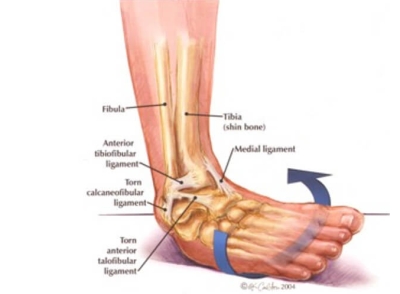

Το διάστρεμμα ποδοκνημικής είναι μια κάκωση η οποία χαρακτηρίζεται από την ρήξη ή την διάταση των συνδέσμων που σταθεροποιούν την ποδοκνημική άρθρωση. Στην συντριπτική πλειοψηφία των περιπτώσεων τραυματίζεται ο έξω πλάγιος σύνδεσμος . Επιδημιολογικά στοιχεία αναδεικνύουν την συχνότερη εμφάνιση σε αθλητές και πιο συγκεκριμένα σε αθλήματα εσωτερικού χώρου (π.χ μπάσκετ, βόλει κλπ.). Σπανιότερα, εμφανίζεται σε άτομα 3ης ηλικίας που το παθαίνουν λόγω μυικής αδυναμίας όπως και σε άτομα με νευρολογικές παθήσεις όπου επηρεάζεται το πρότυπο βάδισης (Εγκεφαλικό Επεισόδιο, Parkinsons, Σκλήρυνση κατα Πλάκας κλπ ).

Ο σύνδεσμος είναι δεσμίδα συνδετικού ιστού, ο οποίος συγκρατεί τα οστά μεταξύ τους. Ο έξω πλάγιος σύνδεσμος της ποδοκνημικής αποτελείται από τρεις δεσμίδες και είναι υπεύθυνος για την σύνδεση των οστών της περόνης, του αστραγάλου και της πτέρνας. Ο έξω πλάγιος σύνδεσμος λειτούργει προστατευτικά έτσι ώστε να μην γίνει υπερβολική ανάσπαση έσω χείλους. Όταν πραγματοποιηθεί αυτή η κίνηση σε υπέρμετρο βαθμό ο σύνδεσμος δεν αντέχει και τραυματίζεται. Αυτή η κατάσταση ονομάζεται διάστρεμμα ποδοκνημικής και ποικίλλει από απλή διάταση (βαθμός 1), μερική ρήξη (βαθμός 2) εως και πλήρη ρήξη (βαθμός 3).